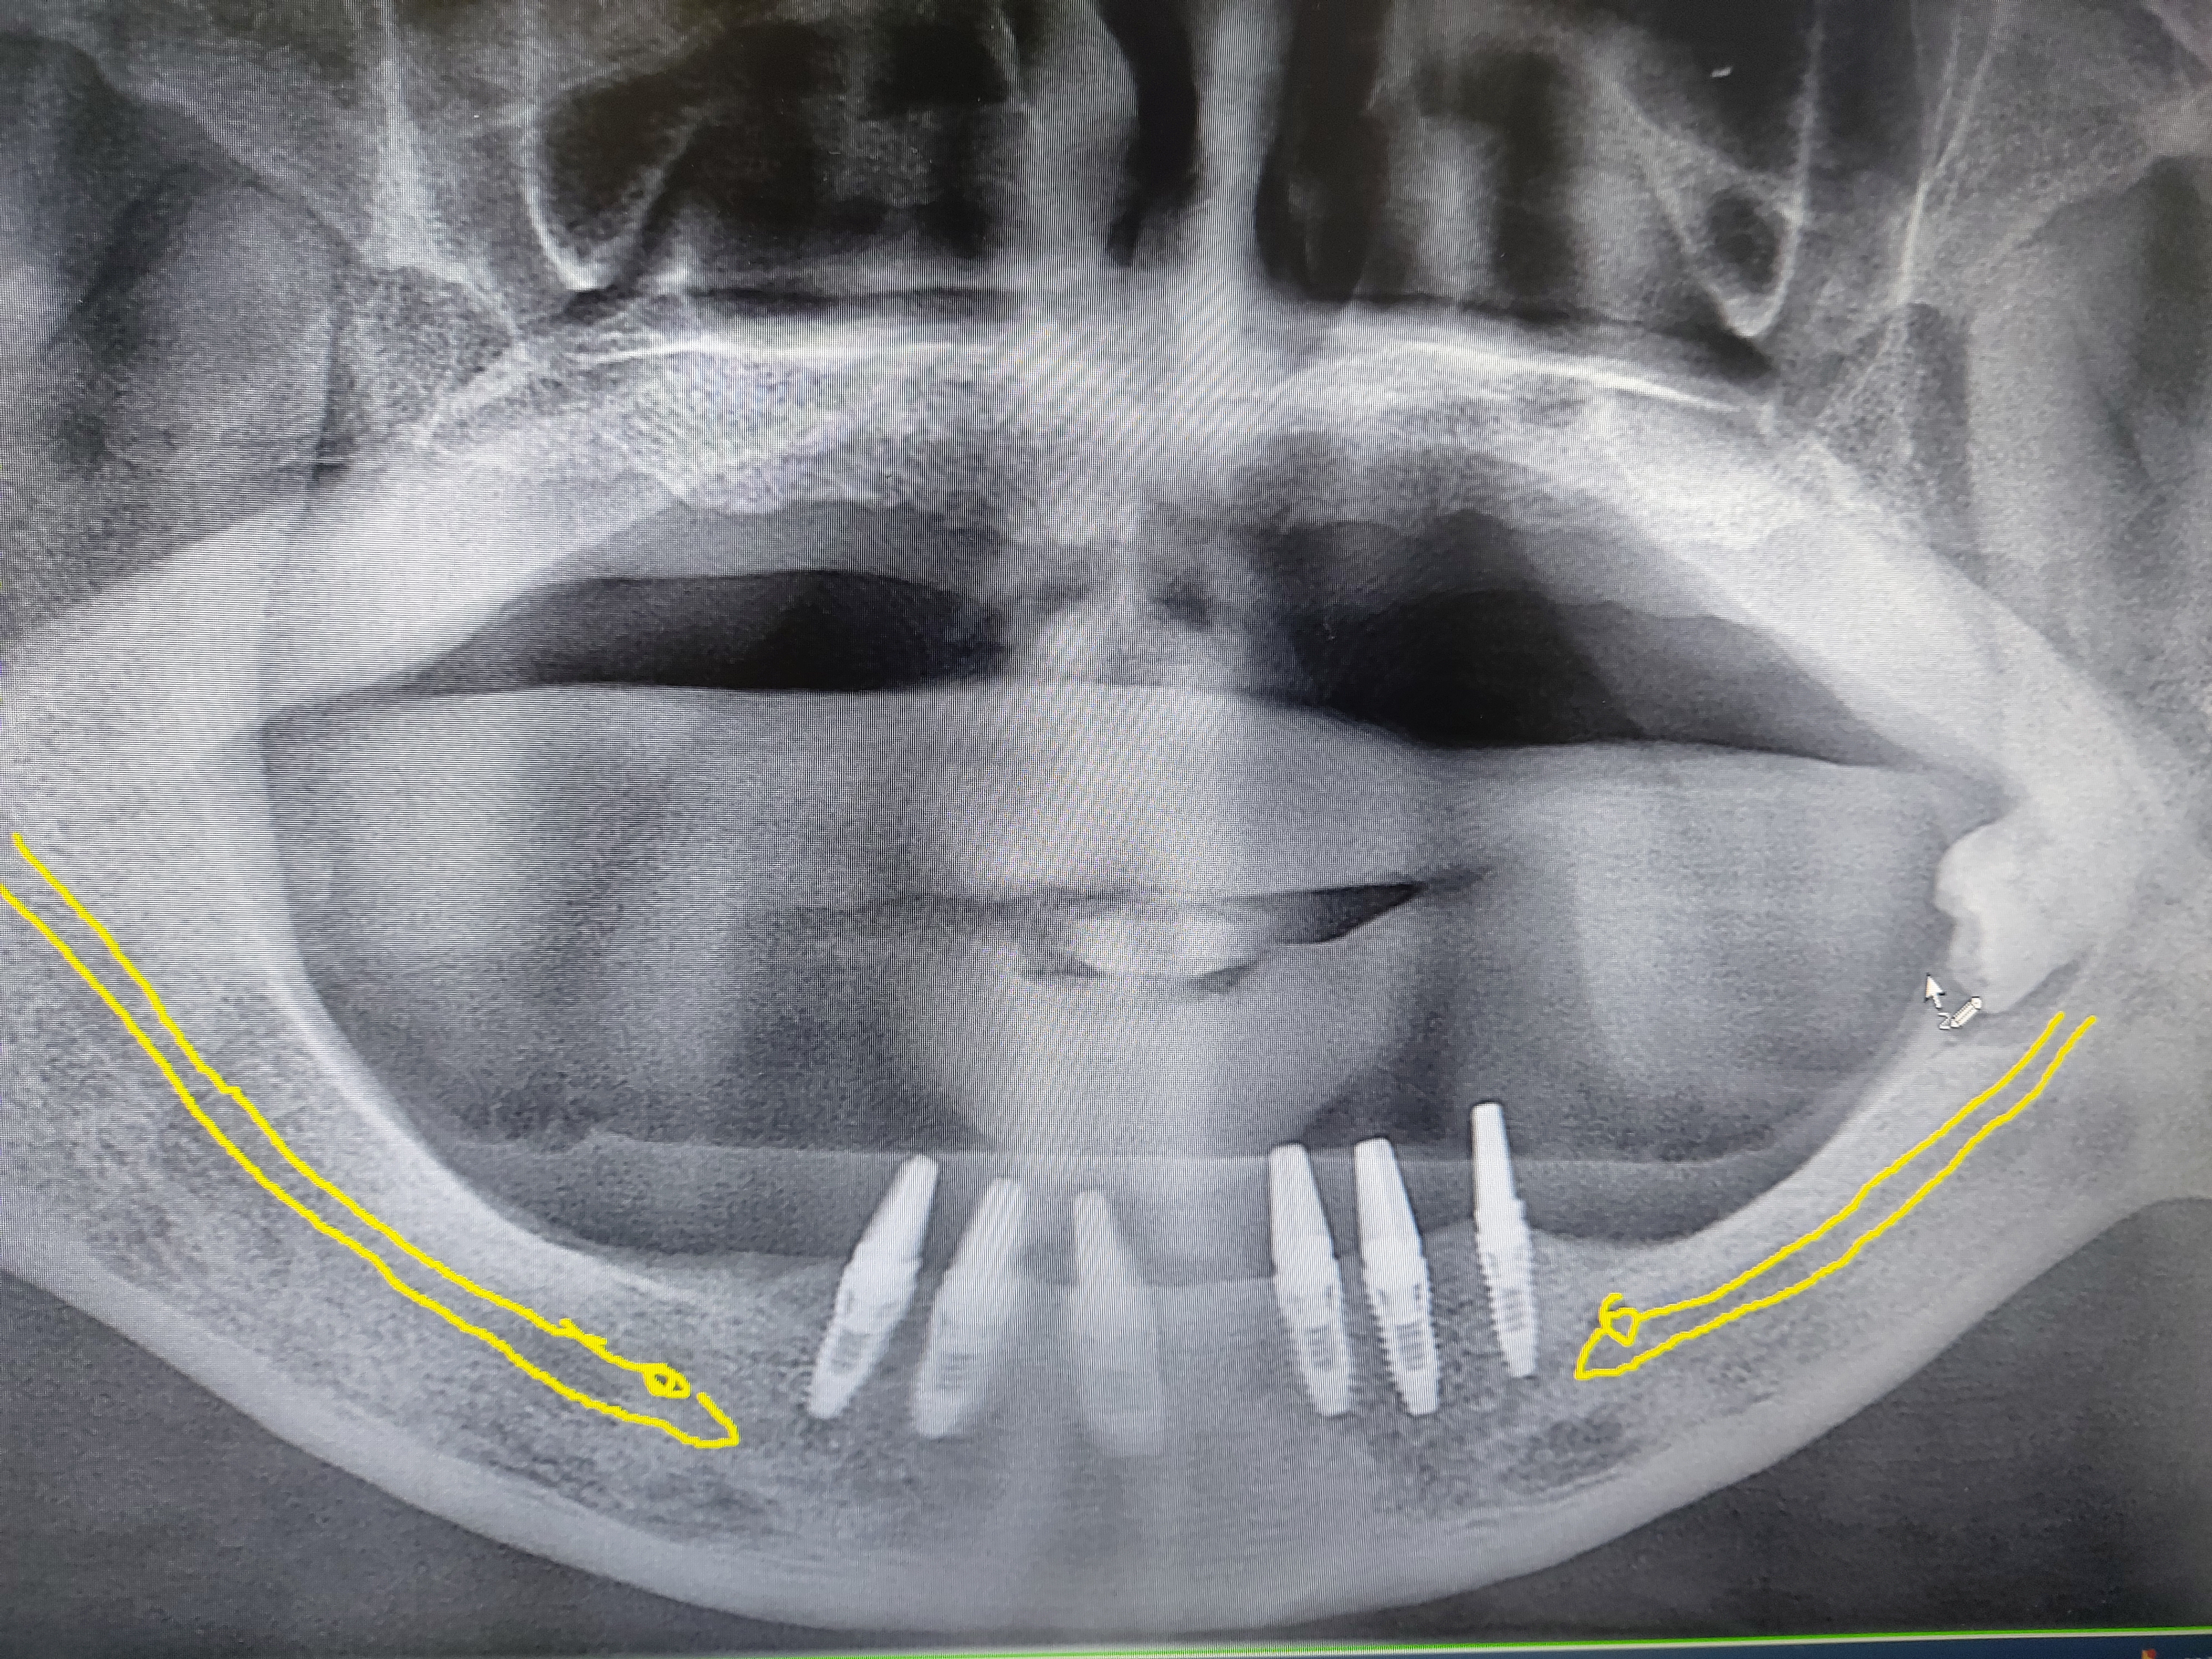

이에 본원에서는 양측 이공(신경) 사이에 6개의 임플란트를 식립하고

실밥을 빨리 풀고 약 4일 뒤 제2소구치 부위까지 임시 치아를 만들어 주었습니다.

약 3개월 뒤에 임시 치아 제거 후 지르코니아 크라운으로 만들어 줄 예정입니다.

이에 본원에서는 구치부의 퇴축으로 임플란트가 불가능 하다고 생각했던 환자도

전치부에 충분한 임플란트를 식립하여 제1대구치 까지 충분한 기능을 할 수 있는 보철물을 만들 수 있음을 보여주는 증례입니다.

수술전 삼차원 씨티를 통하여 이공의 위치 및 신경분지를 잘 확인 하였으며

보통 하악 전치부 식립 부위는 골질이 단단하기에 충분한 드릴링과 주수를 충분히 하연서 식립하였습니다.